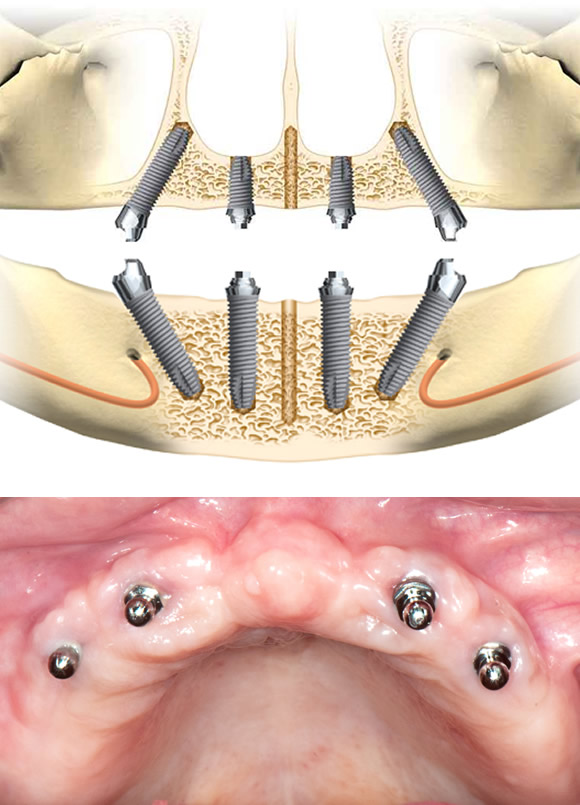

オールオン4によるインプラントの配置

4本のインプラントを埋め込んだお口の中

最終ブリッジを取り付けた状態

インプラントを斜めに埋め込むことにより、噛む力をインプラント上に広く均等に配分できます

▲上下顎にインプラントを4本づつ埋入